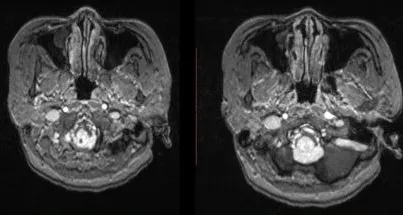

术中影像

术中DSA

术中栓塞前后结果比较